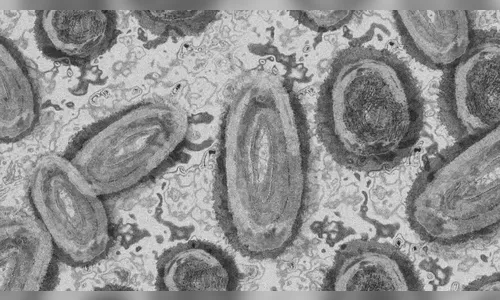

Autor A Secretaria estadual da Saúde (Sesa) confirmou nesta quarta-feira (14) mais três casos de Mpox no Paraná - Foto: Pixabay

A Secretaria estadual da Saúde (Sesa) confirmou nesta quarta-feira (14) mais três casos de Mpox no Paraná. Os novos casos foram registrados em Curitiba (2) e Paranaguá (1).

A Mpox é uma doença viral e a transmissão entre humanos ocorre principalmente por meio de contato com lesões de pele de pessoas infectadas. A infecção causa erupções que geralmente se desenvolvem pelo rosto e depois se espalham para outras partes do corpo. Os principais sintomas envolvem febre, dor de cabeça, dores musculares, dores nas costas, linfadenopatia, calafrios e fadiga.